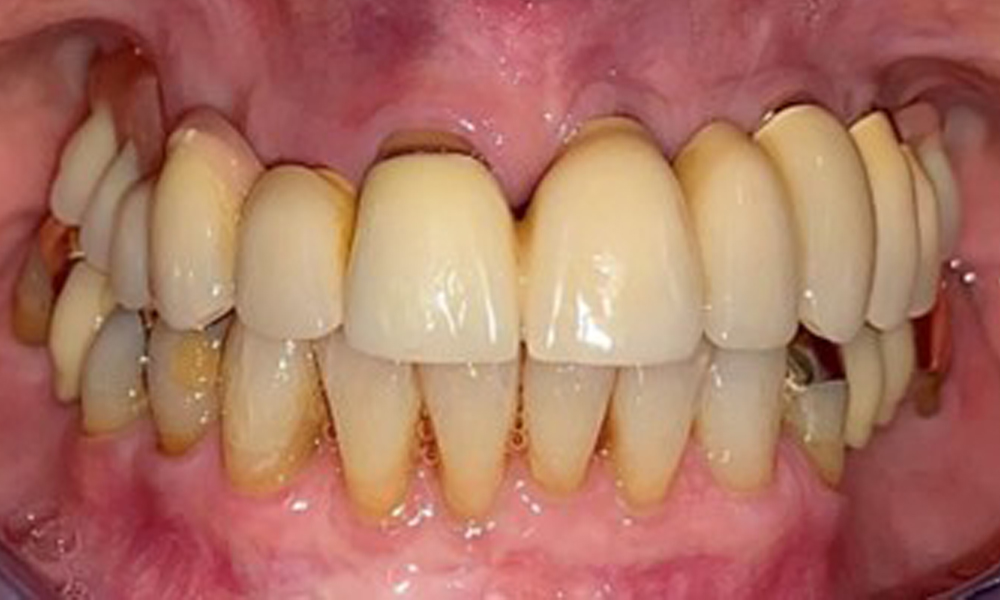

The patient was fitted with a combined removable maxillary telescopic prosthesis more than 25 years ago (Fig. 1, Fig. 2, Fig. 3) and is very happy with her dentures. The patient has an adequate fixed denture for the mandible (Fig. 4).

The dental findings are as follows: Combined removable implant and tooth-supported telescopic prostheses on implants 15, 13, 21, 23, 24, 25 and tooth 11 (Fig. 1, Fig. 2, Fig. 3). The patient was fitted with a fixed mandibular denture. Adequate bridges were present over 37 to 34 and 45 to 47 (Fig. 4), the crown margins were intact and there were no active caries. A composite filling with a marginal gap was present on tooth 43. There was mandibular gingival recession, exposing 1 to 3 mm of root surface. This also applies to 11.

The intraoral mucosa must be examined for possible fungal infections and pressure spots. The dentures must be visually inspected for cleanliness. The present case presented with interdental discolouration, attributed to tea consumption (Fig. 7). The dentures should be professionally cleaned in the dental practice using disinfection and cleaning baths.